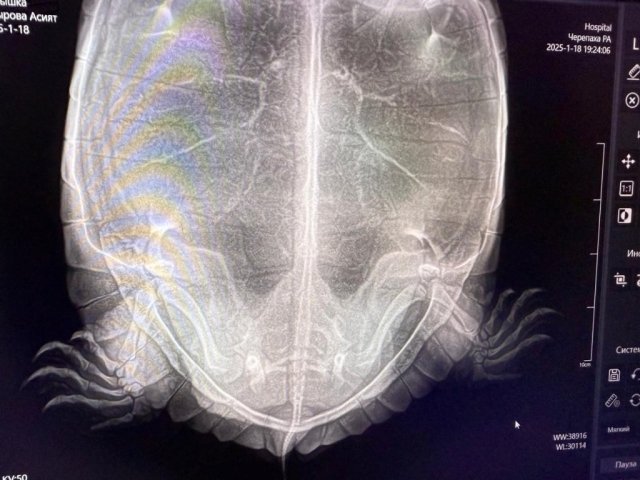

9.Обращались ли в ветклинику? Как называется ветклиника? Как зовут врача (ФИО)? Вводились ли какие-то препараты, если да, то в каких дозировках? Что было сделано по рекомендациям врача? Герпетологов в городе нет, делали рентген, яйца есть.

22a7d346-fe2c-41b3-834c-e9f7e0750714.JPG

@moth 17.01 после курса уколов черепаха снесла 10 яиц, хотя на первоначальном снимке их было 7.

18.01 сделали контрольный снимок, на снимке оставшихся яиц не видно, либо рентген слишком мощный и он просветил все насквозь.